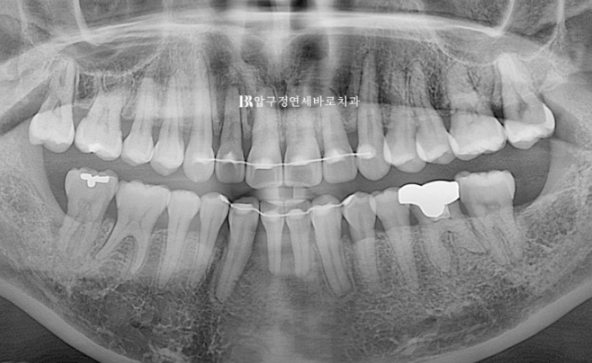

교정 후 엑스레이 입니다.

치아 뿌리 축은 양호하고 많이 흔들리던 앞니는 교정용 철사 유지장치를 붙여놨습니다.

관리를 잘 하시면 큰 불편함 없이 쓸 수 있습니다.

치주염으로 솟아올라와있던 아래 앞니가 정리되면서 뒤로 들어갔고 위 앞니는 뒤로 약 5mm 들어갔습니다.